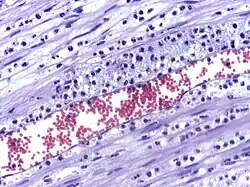

In immunology, leukocyte extravasation (also commonly known as leukocyte adhesion cascade or diapedesis – the passage of cells through the intact vessel wall) is the movement of leukocytes (white blood cells) out of the circulatory system (extravasation) and towards the site of tissue damage or infection. This process forms part of the innate immune response, involving the recruitment of non-specific leukocytes. Monocytes also use this process in the absence of infection or tissue damage during their development into macrophages.

Leukocyte extravasation occurs mainly in post-capillary venules, where haemodynamic shear forces are minimised. This process can be understood in several steps:

The cytoskeletons of the leukocytes are reorganized in such a way that the leukocytes are spread out over the endothelial cells. In this form, leukocytes extend pseudopodia and pass through gaps between endothelial cells. This passage of cells through the intact vessel wall is called diapedesis.[3] These gaps can form through interactions of the leukocytes with the endothelium, but also autonomously through endothelial mechanics.[4] Transmigration of the leukocyte occurs as PECAM proteins, found on the leukocyte and endothelial cell surfaces, interact and effectively pull the cell through the endothelium. Once through the endothelium, the leukocyte must penetrate the basement membrane. The mechanism for penetration is disputed, but may involve proteolytic digestion of the membrane, mechanical force, or both.[5] The entire process of blood vessel escape is known as diapedesis. Once in the interstitial fluid, leukocytes migrate along a chemotactic gradient towards the site of injury or infection.